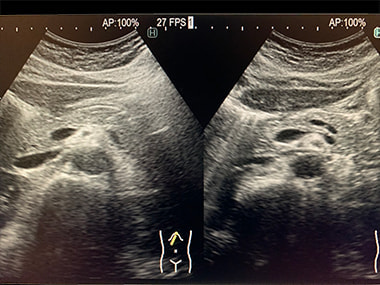

腹部エコー検査:

腹部臓器(肝臓・胆のう・膵臓・腎臓・脾臓)、腹部大血管、骨盤病変(膀胱・前立腺・子宮・卵巣)、リンパ節などに異常病変がないかを検査します。